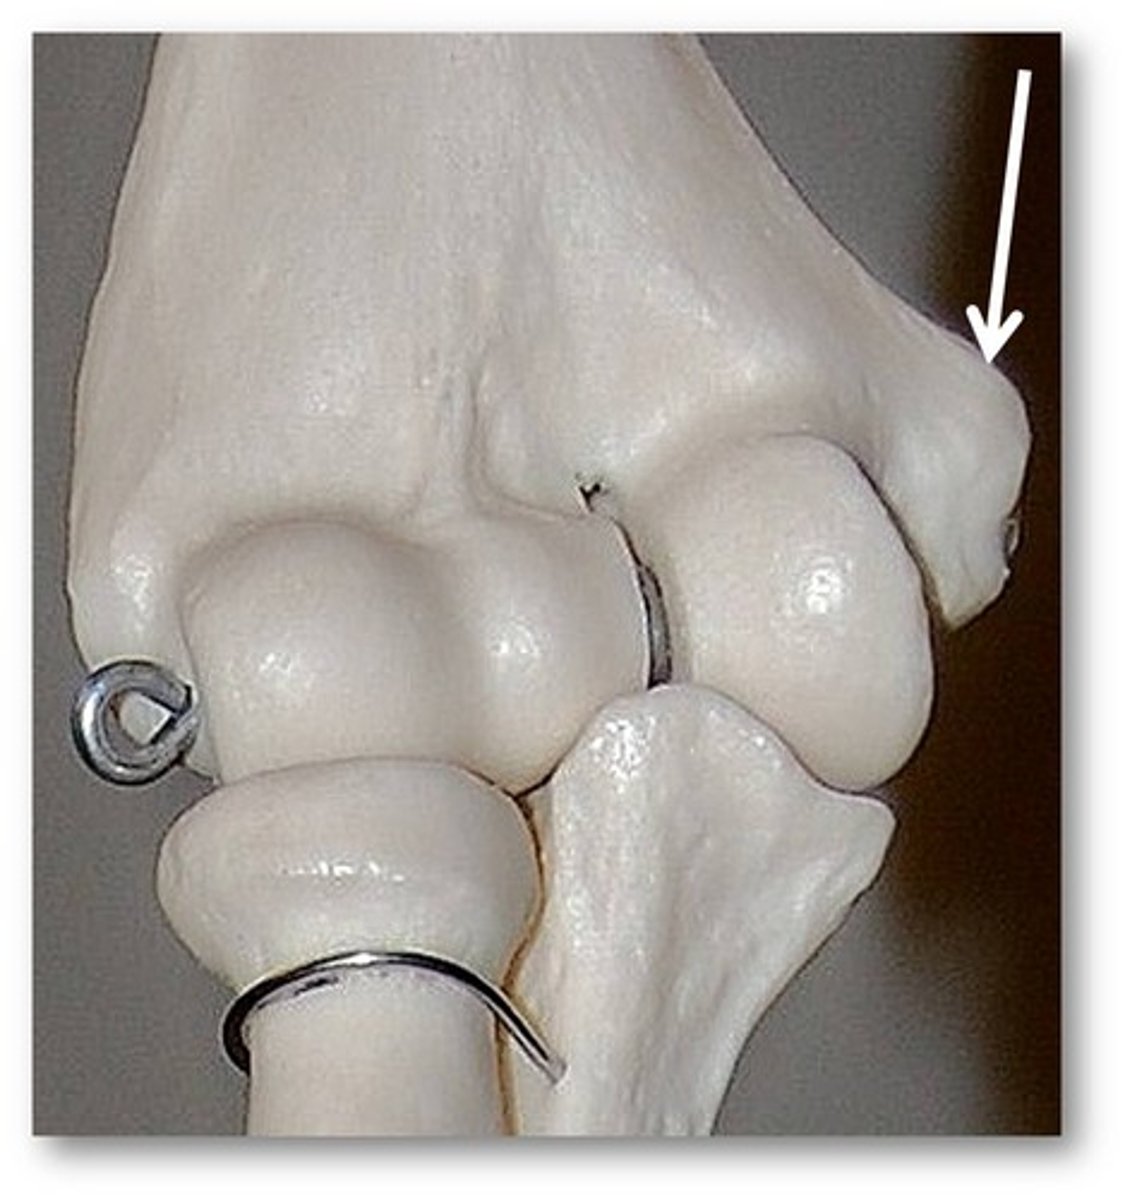

medial condyle of femur

lateral condyle

medial epicondyle

lateral epicondyle

intercondylar fossa

tibial plateau

medial condyle of tibia

lateral condyle of tibia

intercondylar eminence of tibia